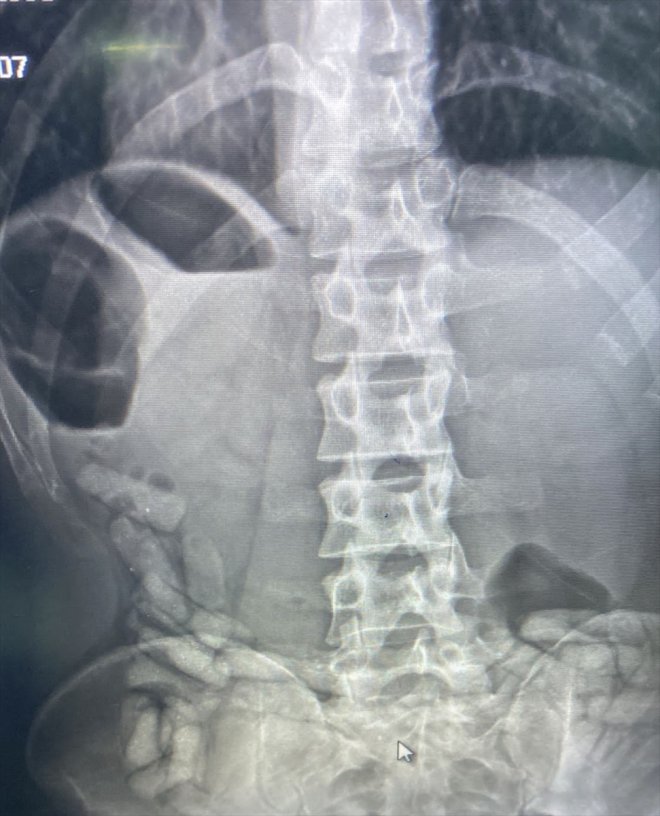

Gözaltına alınarak Dr. Yaşar Eryılmaz Doğubayazıt Devlet Hastanesi'ne götürülen şüphelinin çekilen röntgeninde vücudunun çeşitli yerlerinde uyuşturucu kapsüller bulunduğu belirlendi.

Yapılan çalışma sonucu A.G'nin mide ve bağırsağında 55 kapsül halinde 432 gram afyon sakızı bulundu. Adliyeye sevk edilen zanlı, çıkarıldığı sulh ceza hakimliğince tutuklandı.